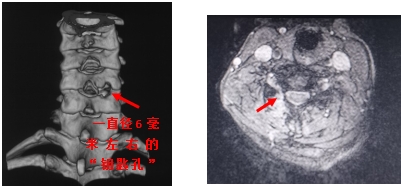

颈椎MRI示颈5-颈6椎间盘突出,压迫相应硬膜囊和神经根(红色箭头表示突出的间盘)

术后复查颈椎三维CT和颈椎MRI,可见第5-6颈椎间开了个类似钥匙孔大小的洞,并且神经压迫得到完全解除